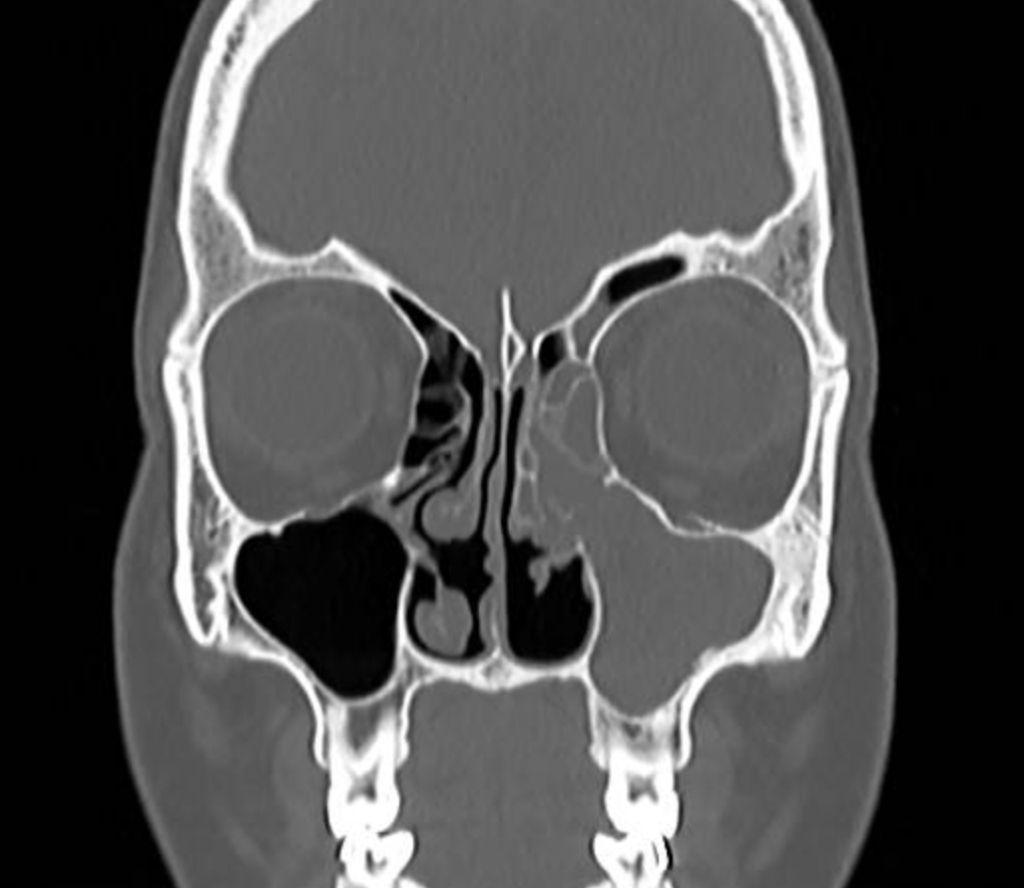

Concha bolhosa (concha média pneumatizada)

Esse achado aparece menos no vocabulário popular, mas é mais comum do que parece. A concha média é outra estrutura interna do nariz, e em algumas pessoas ela vem “pneumatizada” — ou seja, com uma bolha de ar dentro. Quando essa bolha é grande, ocupa espaço e pode obstruir o caminho do ar e a drenagem dos seios da face.

Em laudo, costuma aparecer como “concha média pneumatizada bilateralmente” ou “concha bolhosa”. Nem toda concha bolhosa precisa de cirurgia — muitas pessoas convivem bem com isso. Mas quando há sintomas associados (obstrução, sinusites recorrentes, dor facial), pode ser parte da indicação cirúrgica.